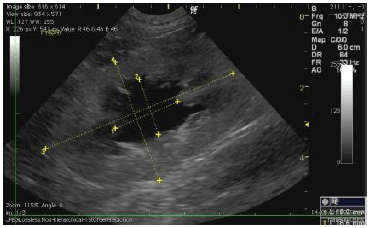

腎臓の超音波(エコー)画像です。

左が正常な腎臓、右が今回の猫の腎臓です。 真ん中の黒い部分が広がっていますが、これは結石によって先へ流れなくなってしまった尿が腎臓に溜まっているためです。 この状態が進行するほど、腎臓の機能は失われていきます。

上が正常な腎臓、下が今回の猫の腎臓です。 真ん中の黒い部分が広がっていますが、これは結石によって先へ流れなくなってしまった尿が腎臓に溜まっているためです。 この状態が進行するほど、腎臓の機能は失われていきます。 |